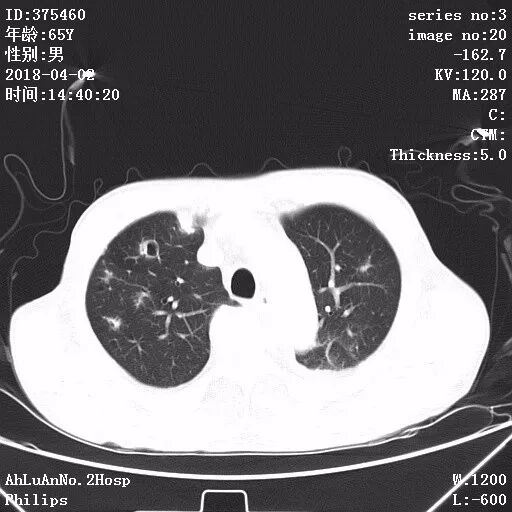

患者男,65岁,因“咳嗽、咳痰1月余,发热1周”入院。

两肺可见多发斑片状及气囊样阴影,部分气囊样影内可见气液平面,两侧胸膜腔可见少量液性密度影聚集。

结果:金黄色葡萄球菌肺炎

显示,白细胞计数和中性粒细胞百分比升高,可有核左移及中毒颗粒。本病的胸部X线特征常表现为肺段或肺叶实变,或呈小叶样浸润,其中有单个或多发的液气囊腔。

X线阴影的易变性是本病的另一重要特征,其常表现为一处炎性浸润消失而在另一处出现新的病灶,或很小的单一病灶发展为大片阴影。